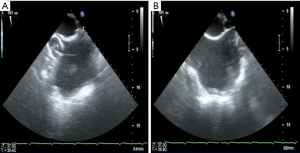

Thoracotomy and visualization of the TV

Being on CPB, a limited right antero-lateral thoracotomy is performed. Lungs are deflated and the RA is identified by pushing on the atrial wall with a long forceps and echo control. Both Fogarty catheters are inflated with saline and retracted under echo control into the SVC and IVC to induce total CPB (Figure 4A,B). The pericardium is not dissected from the RA, but incised directly. Using a retractor, the TV is visualized and repair is being performed on the beating heart.